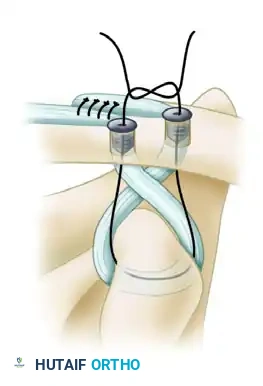

- Fixation: While maintaining the reduction, secure the graft limbs within the clavicular tunnels using soft tissue interference screws (typically 5.5 mm or 6.25 mm PEEK or biocomposite screws).

- Insert the first screw into the posterior (conoid) tunnel, bringing the whipstitch sutures up through the cannulation of the screw.

Secure the graft with a soft tissue interference screw in the posterior tunnel. The sutures are brought through the cannulated screw to allow for secondary fixation.

- Assess the reduction and screw placement. Once confirmed, place the second interference screw into the anterior (trapezoid) tunnel.

- Secondary Fixation: Tie the high-strength sutures from the medial and lateral limbs together over the bony bridge between the two tunnels to provide a secondary node of fixation and back up the interference screws.

Interference screw fixation of the graft to the clavicle, followed by tying the high-strength sutures over the intervening bone bridge for augmented construct security.